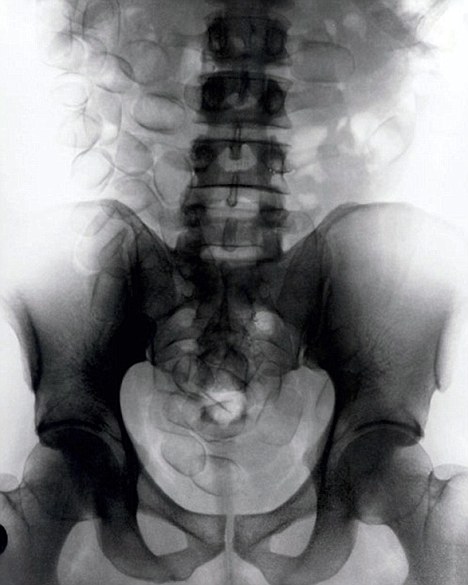

現(xiàn)年30歲的菲達(dá)利斯(Fidelis Ozouli)冒著生命危險將重達(dá)1公斤的毒品吞下,被抓后卻辯稱不知道吞下的是毒品。當(dāng)時,曼徹斯特機(jī)場的海關(guān)人員看到毒販菲達(dá)利斯臃腫的肚腩,顯得很不自然,于是開始懷疑。檢查人員用X射線機(jī)照他的胃部時,發(fā)現(xiàn)了大量可卡因。目前他已被送往附近醫(yī)院,以確保排出所有的毒品。

這名男子還將毒品藏在幾十個避孕套里,估計純度為78%,價值25萬英鎊。毒販后來被帶到曼徹斯特皇家法庭,自稱來自尼日利亞,目前在倫敦生活和學(xué)習(xí)。他承認(rèn)攜帶A類毒品入關(guān)確實犯了法,但否認(rèn)他吞下的是毒品。目前他已經(jīng)被英國警方正式逮捕,案件已轉(zhuǎn)交給毒品稽查部門,預(yù)計他將被判入獄10年。